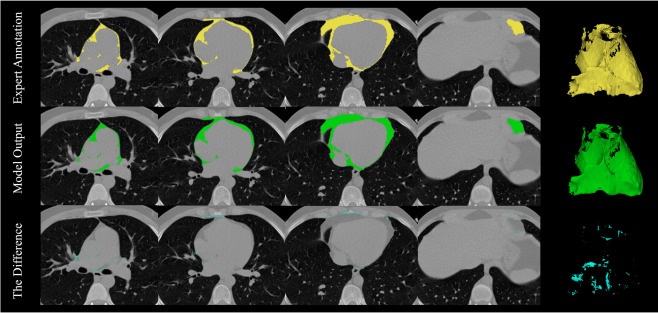

- AI-Reconstructed Medical Images May Be Unreliable